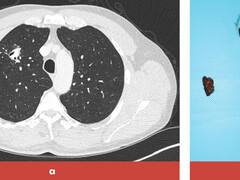

Hemoptoë bij een man afkomstig uit Servië